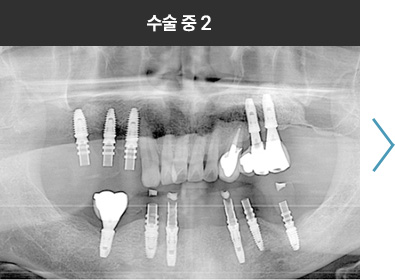

BMP를 이용한 수술 사례      I

치료 기간 : 2023.03.22 ~ 2023.09.15

* 상기 사례의 경우, 해당 의료기관에서 진료를 한 환자분의 동의를 얻어 사용되었습니다. * 치료 전후의 사진은 동일 인물과 동일한 조건에서 촬영 되었음을 알려드립니다.

* 모든 수술 및 시술은 개인에 따라 부작용고지 : 임플란트치료는 치료 후 감염,

염증, 연조직합병증, 출혈, 감각이상 등의 부작용이 있을 수 있습니다.

의료진과 충분히 상의 후 신중하게 결정하시기를 바라겠습니다.